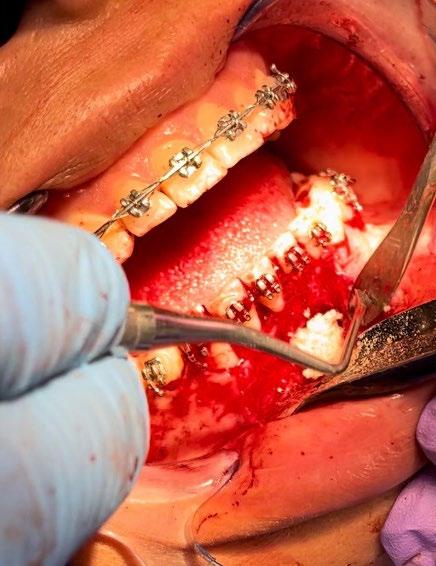

El tratamiento se realizó en las siguientes fases: la fase prequirúrgica incluyó la alineación, nivelación y la

extracción de los segundos premolares superiores e inferiores, con cierre de espacios. En la fase quirúrgica, se realizó una mentoplastia de avance e implantes en la zona malar. La fase postquirúrgica consistió en el detallado-retención. La aparatología utilizada fueron brackets de prescripción Roth .022 × .028; se colocaron bandas en los primeros molares superiores e inferiores, con tubos punteables en los O.D. 16, 26, 36 y 46, y tubos bondeables en el O.D. 27, además de un arco transpalatino y un arco lingual.

El tratamiento se realizó en las siguientes fases: la fase prequirúrgica incluyó la alineación, nivelación y la extracción de los segundos premolares superiores e inferiores, con cierre de espacios.

Previa asepsia y antisepsia, más colocación de campos en forma habitual, mediante infiltración troncular y de forma local, se realiza incisión

marginal con descarga lineal para levantar un colgajo seminewman (Figura 3). Se realiza ostectomía y osteotomía para liberar el órgano dentario retenido y facilitar su extracción (Figura 4). Una vez fuera de la cavidad bucal, se realiza tratamiento de conductos y obturación. De forma simultánea, se lleva a cabo la extracción atraumática del órgano dentario 73 (Figura 5) y la preparación alveolar del lecho receptor para recibir el órgano dentario a trasplantar bajo parámetros quirúrgicos (Figura 6).